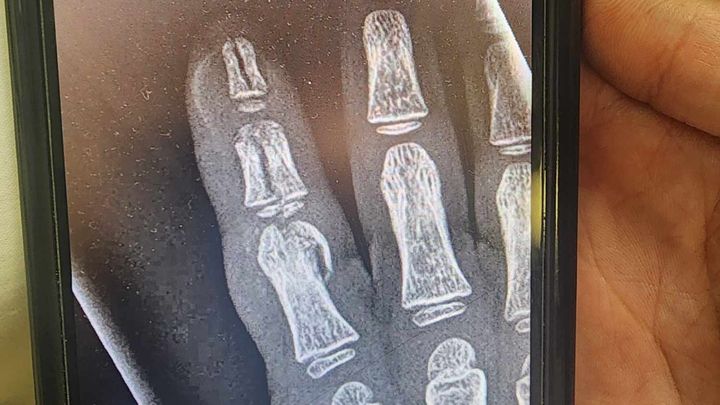

Max had a bowling accident on Tues Jan 14th. His pointer finger was smashed between a bowling ball and the floor after a slip & fall. At the Emergency Room they discovered his 3 bones were broke and they could not stitch up the gash. Jan 15th he had to see the surgeon in Traverse City to evaluate this break. The surgeon needs to do surgery first thing Monday so Max doesn't lose his finger. The surgery and doctor bill copay are adding up daily. The $3,500 is an approximate just to do the surgery on Monday, which needs paid prior to it being done. His mom & dad, Jilleanna & Casey, have tried everything to find this money to no avail. PLEASE, help by donating any money you can to fix Maxwell's finger. They canceled his Great Wolf Lodge trip on the 29th to use the money to pay for the trip to Traverse, food, and a payment to the surgeon today. If you prefer, cash or checks can be sent to: